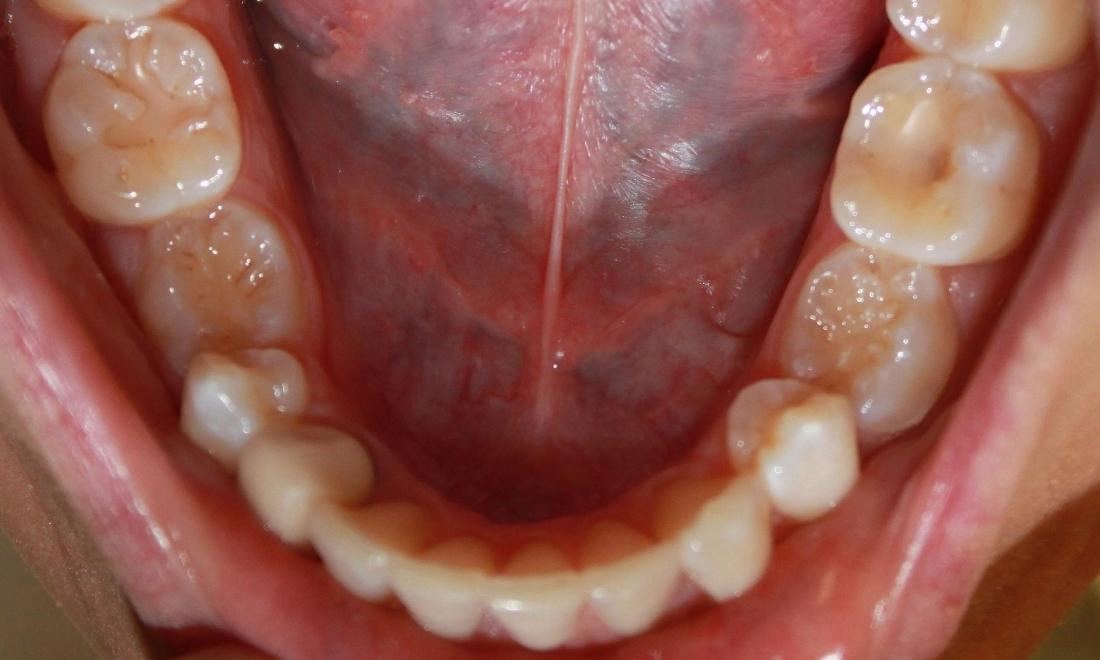

Crowding-- Some potential issues: Buildup of plaque and tartar, harbors harmful periodontal bacteria, risk of periodontal disease, tooth, and bone loss. After one year of Invisalign treatment, teeth have aligned properly for a healthier mouth.

crowded lower front teeth | invisalign dentist vienna lower front teeth after invisalign | dentist in vienna va